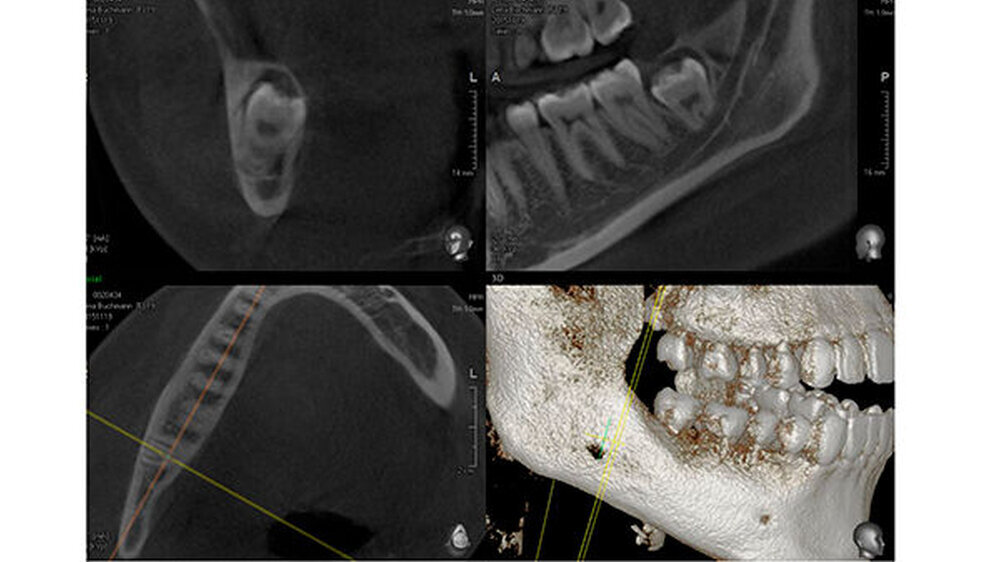

Aufgrund der engen Lagebeziehung der Weisheitszähne 38 und 48 zum Nervus alveolaris inferior (Abbildung 1) wurde zur weiterführenden Diagnostik eine digitale Volumentomografie (DVT) in der Praxis von Dr. Burkard Langenfeld in Friedrichshafen durchgeführt (Abbildungen 2 und 3).

Auf der DVT-Aufnahme zeigte sich vor allem in regio 48 der extrem Nerv-nahe Bezug und eine sehr tief impaktierte Lage des Zahns zum Ramus. Aufgrund dieser Befunde wurde eine Verplattung wegen der möglichen iatrogenen Bruchgefahr des Unterkiefers zur Stabilisierung des Unterkiefers mit der Patientin präoperativ besprochen.